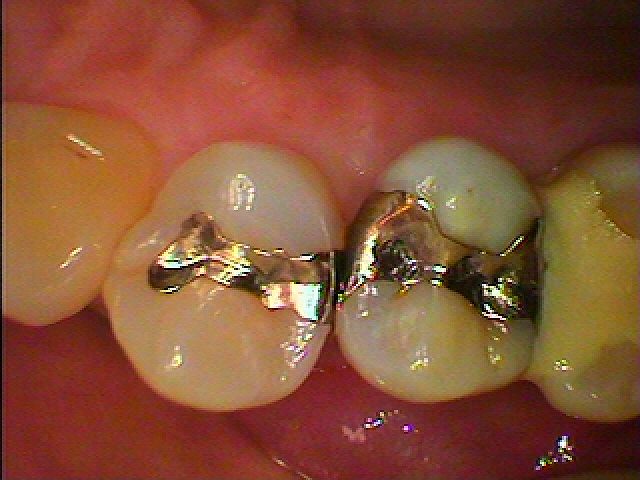

セラミックInのセットになります。右上小臼歯部になります。| |広島市安佐南区の歯科医院 セラミックInのセットになります。右上小臼歯部になります。 トップ お知らせ・ブログ セラミックInのセットになります。右上小臼歯部になります。 セラミックInのセットになります。右上小臼歯部になります。 Web診療予約 初めての方へ 選ばれ続ける理由 院内設備について 歯が痛いしみる一般歯科 歯がぐらぐらする歯周病 健康な歯を保ちたい予防歯科 子供の虫歯予防をしたい小児歯科 銀歯をセラミックに審美歯科 白い歯を目指しませんか?ホワイトニング 矯正専門医がいるので安心矯正歯科 抜けた歯を補いたいインプラント・入れ歯 医院案内 スタッフ紹介 メリィハウス歯科クリニックオフィシャルホームページ ラベンダー歯科クリニックオフィシャルホームページ お知らせ・ブログ ホーム 診療科目 一般歯科 歯周病治療 予防治療 小児歯科 審美治療 ホワイトニング 矯正歯科 入れ歯・インプラント マウスピース矯正 初めての方へ 院長・スタッフ 設備紹介 医院案内・アクセス メニューを閉じる